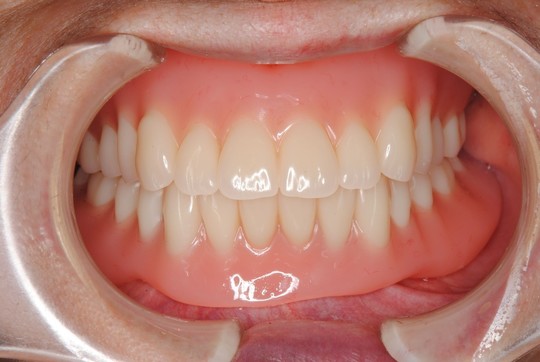

治療後

口の中で動きにくく外れにくい入れ歯ができました。

下顎義歯は残っている歯に「エラアタッチメント」

特殊な装置を組み込んで入れ歯の安定を図りました。